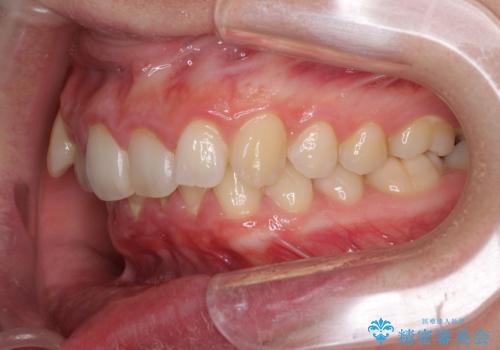

- 八重歯を気にして来院された患者様です。

八重歯の後ろの歯を1歯抜歯し、補助装置(リンガルアーチ)を用いて八重歯の位置を改善し、その後インビザラインにより矯正治療を行うこととしました。

下顎前歯が1本欠損したスリーインサイザーという状態であるため、上下の前歯の咬み込みが深くなったり、奥歯の咬み合わせが理想的なものとならなかったりという仕上がりになってしまいます。

前歯の見た目や奥歯の咬み合わせに、患者様が違和感を感じない状態として治療を終えました。